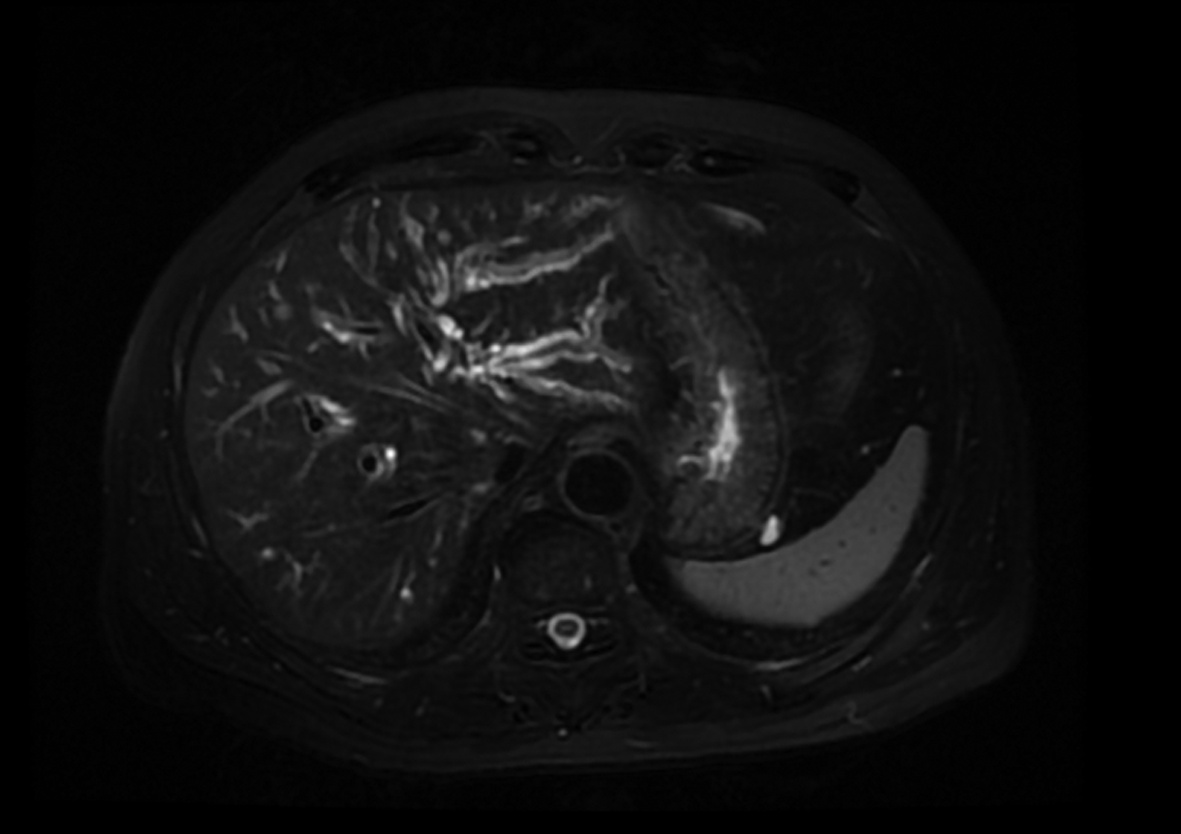

Local embolization combined with targeted comprehensive immunotherapy in treatment of sarcomatoid hepatocellular carcinoma: A case report

Jin LEI, Linzhi ZHANG, Yinying LU, Bowen CHEN, Shi ZUO

2022, 38(4): 880-882. DOI: 10.3969/j.issn.1001-5256.2022.04.026

Abstract(1335) HTML (456) PDF (3487KB)(84)

Abstract: